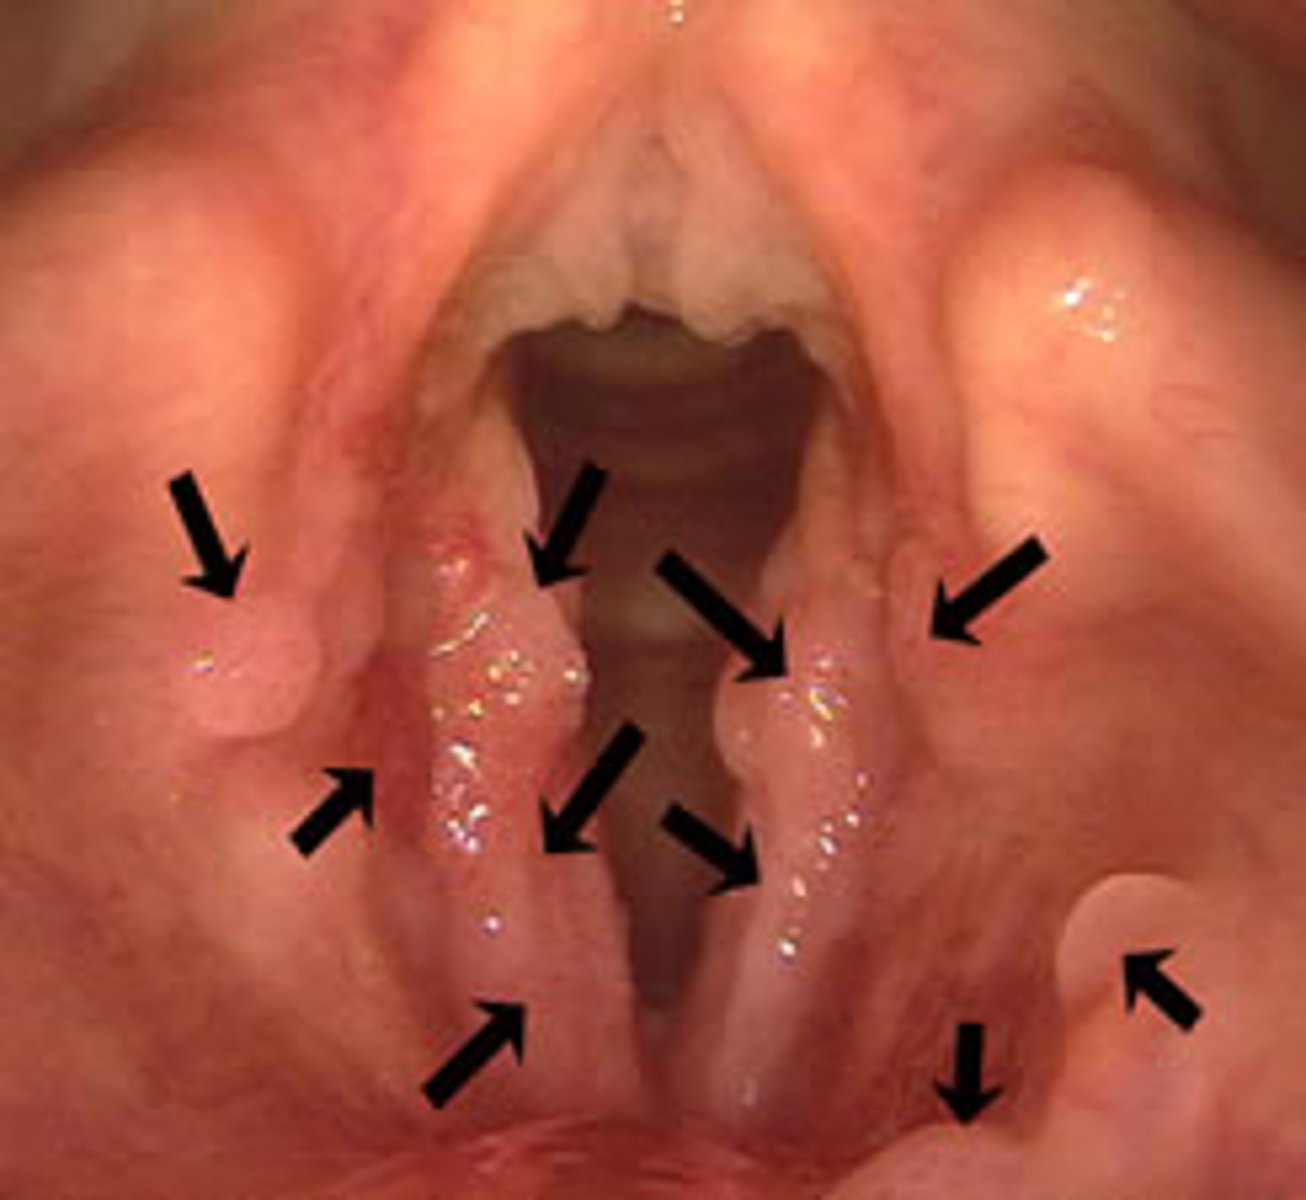

What HPV subtypes cause condyloma?

HPV 6 and 11

How do you treat condyloma?

excision, cryotherapy, trichloroacetic acid, and imiquimod (benign)

recurrent respiratory papillomatosis (RRP)

papilloma on the vocal cords, larynx, and respiratory tract that are transmitted from mother to child at birth (HPV 6 and 11)

What HPV subtypes cause oral papilloma?

How do you treat oral papilloma?

surgical removal or cryotherapy (benign)